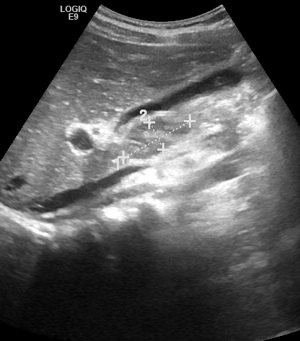

Davide � un

ragazzo di 12 anni, che vediamo in PS per 4 giorni di febbre elevata

con brivido e dolore al fianco sinistro. L'ecografia addominale

(Figura 1) evidenzia �all'ilo

epatico linfonodi ingranditi e nella

milza alcune aree sfumatamente ipoecogene da possibili

localizzazioni linfomatose.� Figura 1. L�ECO

addominale evidenzia nella milza alcune aree sfumatamente ipoecogene

Eseguiamo quindi un'ecografia addominale (Figura 3): �Milza

ingrandita e disomogenea con alcune areole rotondeggianti,

sfumatamente ipoecogene. All'ilo epatico presenza di alcuni linfonodi

ingranditi ovalariformi.�